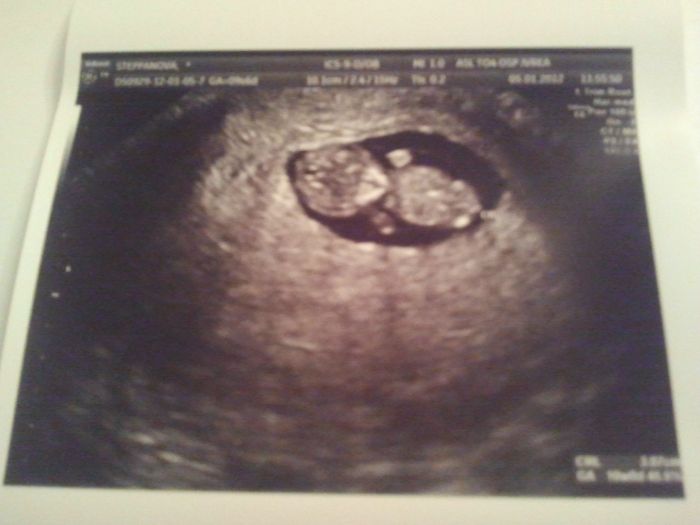

Ahojky a krasny den vsem zdravim z Italie repektive Torina...jak se mate tehulky?ja celkem fajn dala jsem si praci a obvolala dost doktoru tady v Torine a vyptavala jsem se co se stane nebo enstane kdyz vysadim utrogestan,chtela jsem to slyset od vice doktoru jak se rika vic hlav vic vi.takze mi rekly ze to klidne muzu vysadit protoze placenta zacina pracovat kolem 12 tydne a ja uz jsem ve 11 tydnu takze to zas takovy velky problem neni a podle doktoru jestly miminko prezije ci ne nezavisi na utrogestanu ale na jinych faktorech,utrogestan jen pomaha tehotenstvi udrzet v prvnich mesicich tehotenstvi.takze jsem to vysadila a jsem opravdu zvedava jak bude prcek reagovat snad dobre.jinak dnes jsem si obednala angelsounds, jestly nevite co to je , tak je to aparat kterym muzete od 12 tydne poslouchat srdicko miminka a i si ho nahrat na cd takze vam zustane na vzdy, ale to hlavni je ze muzeme byt porad klidne ze miminka jsou v poradku a ne trnout do dalsich kontrol nebo ultrazvuku alespon me to pomuze byt vic klidna.jinak dneska jsem vstavala az ve 12 v poledne takze miminko bude spac, holky celou noc jsem jedla same dorty a jak byly dobry,ten muj mrnous je desne na sladky a pak zeleninu a ovoce hlavne grepy jim po kilech a to je vic nez 3 roky co jsem ho nejedla a ted porad.jeste jednou vas vsechny zdravim a pridam fotecku z ultrazvuku co jsme byly minuly tyden ve ctvrtek.....

holky tak dobrou pro dnešek. Jo a ta fotka z UZ co tady Petra dala je super...je dělana skrz břichoi nebo vnitřkem? já mám na te fotce videt jen bilý flek...vůbec to nevypada jako človek to moje.. tohle je fotečka vskutku už na ukazování :-)

spatne tak byvat nebude.....je to sice invidualni, ale od 12 tydne to vetsinou prechazi.....sice u nekoho to pretrvava az do konce........ Ja mam take takovou fotecku a delal ji vnitrne. Byla jsem v 9+4 a mam jit zase 17. ledna po 14cti dnech, chodim tam celkem casto.

Dobrý ráno holky, Katko tak to bude tím že Vám dělal UZ vnitřně..asi lepší viditelnost...búúú...já chci taky takovou fotečku jako máte vy...